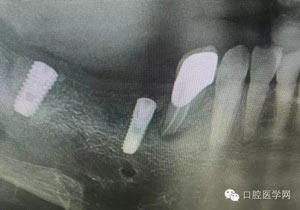

病例1:患者迫切希望保留自己的這一顆牙齒,根尖周陰影比較大,二度松動.而且旁邊有種植修復(fù)體,和患者溝通好后,治療好后觀察一個月后冠修復(fù),因為有種植的后期修復(fù),所以有了機會觀察,術(shù)后三個月和術(shù)后四個月,根尖恢復(fù)的還算不錯,希望能夠繼續(xù)觀察下去.這樣子的病例,做的時候我們一定要非常的小心,和患者要有充分的溝通以及不同科室的溝通然后決定怎么樣做比較好,假如就是出現(xiàn)了問題,到時候我們也比較好處理些,免得我們自己到時候不好收場。